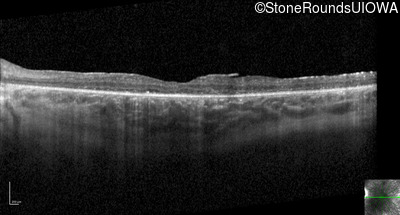

Optical Coherence Tomography - Right - 20/50

Exemplar / OCT Stack

OCT Stack